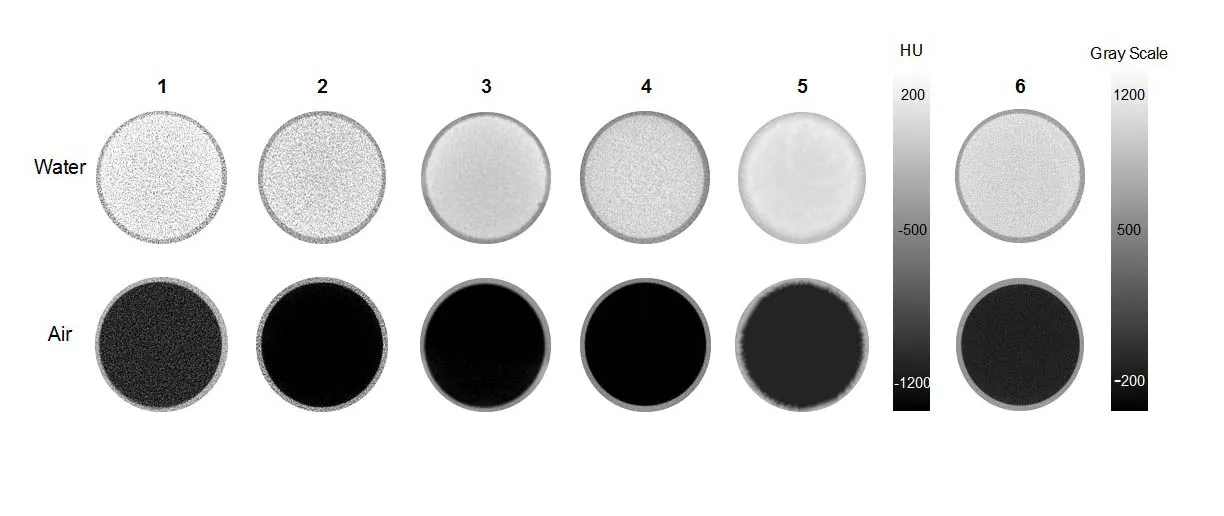

Gray scale of PET CT images